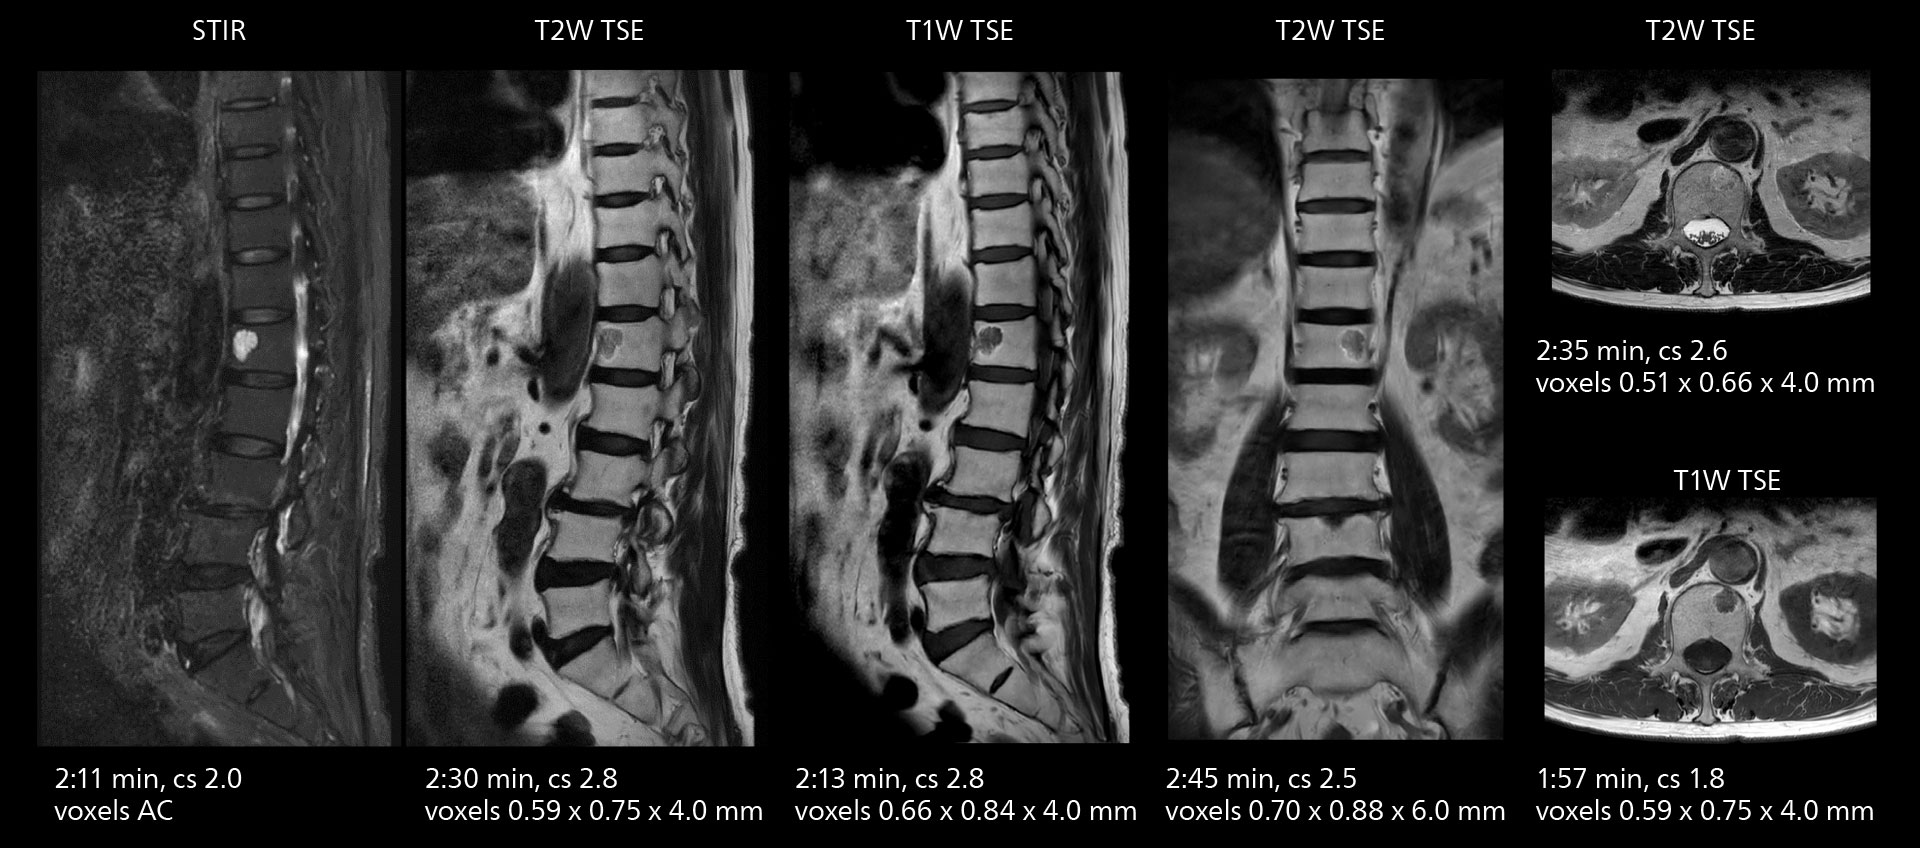

Sannodai Hospital radiologists had been very satisfied with their Ingenia 3.0T with Compressed SENSE, however after acquiring SmartPath to Elition X they have demonstrated improved image quality and even higher speeds in imaging studies throughout the body, according to Dr. Makuuchi. “Generally, we were impressed by seeing that images are very sharp and have higher SNR than we used to get with our Ingenia 3.0T system,” he notes. “We were delighted to see that high image quality can be obtained in a short time thanks to the Elition with its powerful An example of increased imaging speed is in knee studies. “There is a definite scan time reduction for T2* mFFE and proton density TSE – both of these sequences benefit from much shorter repetition times,” he reports.

gradients. Some high resolution examinations that were not possible before dueto their longer scan time, are now routinely performed with the upgraded system.”

The value of the Elition X gradients is also evident in DWIBS studies. “The fact that we can consistently obtain distortion‐free DWIBS while reducing imaging time at three coronal stations is excellent,” Dr. Makuuchi says. “In these patients, it’s also important that the application of Compressed SENSE to T2‐weighted, STIR and mDIXON sequences has no impact on the examination time of whole‐body imaging. As a result of the increased speed and higher image quality we realize, DWIBS studies have now become routine examinations.”

With SmartPath to Elition X the team can obtain excellent quality DWIBS imaging and reduce imaging time. Other sequences also fit in the examination slot. This case shows left paravertebral neurogenic tumor and Th10 vertebral hemangiomas.